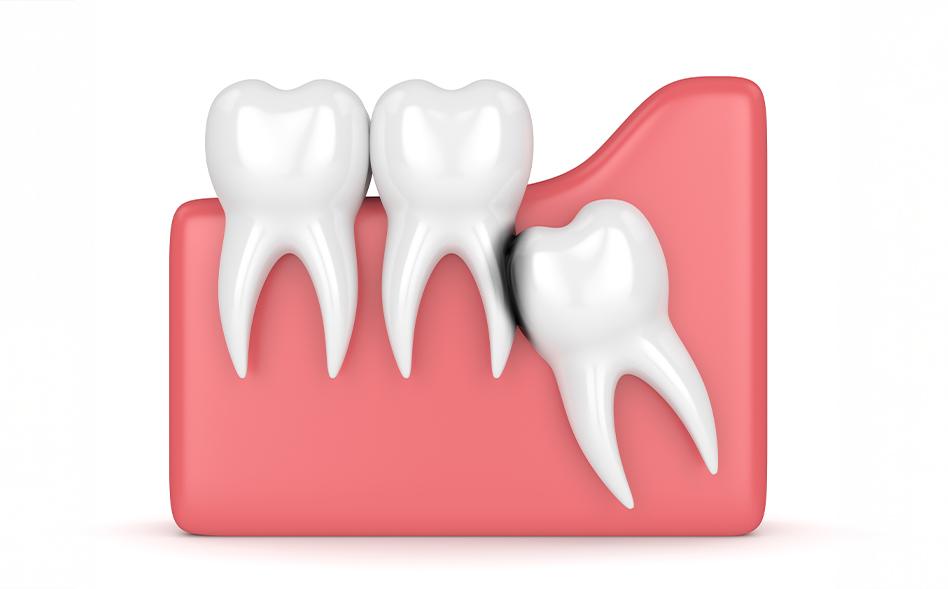

• Impaction – The tooth becomes trapped beneath the gum or jawbone

• Partial eruption – Only part of the tooth emerges, creating an opening where bacteria can enter

• Crowding – Limited space causes pressure on neighbouring teeth